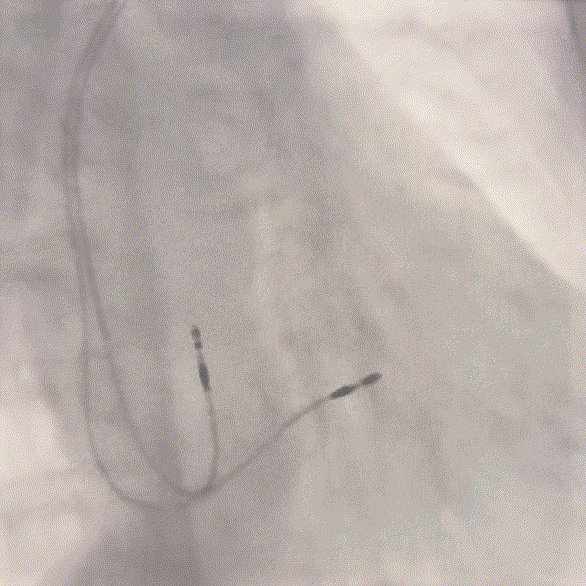

术后植入位点

图11

术后即刻参数QRS:101ms,达峰时间:64ms,SV:39ms。